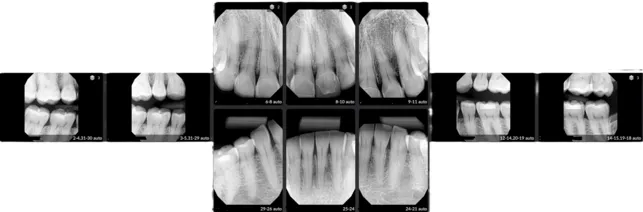

It is important to know that your doctor is keeping up with the constant and rapid advancements in modern technology. Digital x-rays are just one more advantage you will have at your disposal when you visit our office. Instead of using a conventional film, we use a special computer sensor which puts the x-ray picture directly into the computer and which allows us to reduce the amount of harmful radiation by nearly 90%. Since the pictures are in the computer, we can enhance the images to better diagnose conditions--often before they become problems. This proves to be much more convenient for you because the x-rays can then be displayed on the computer right in front of you!